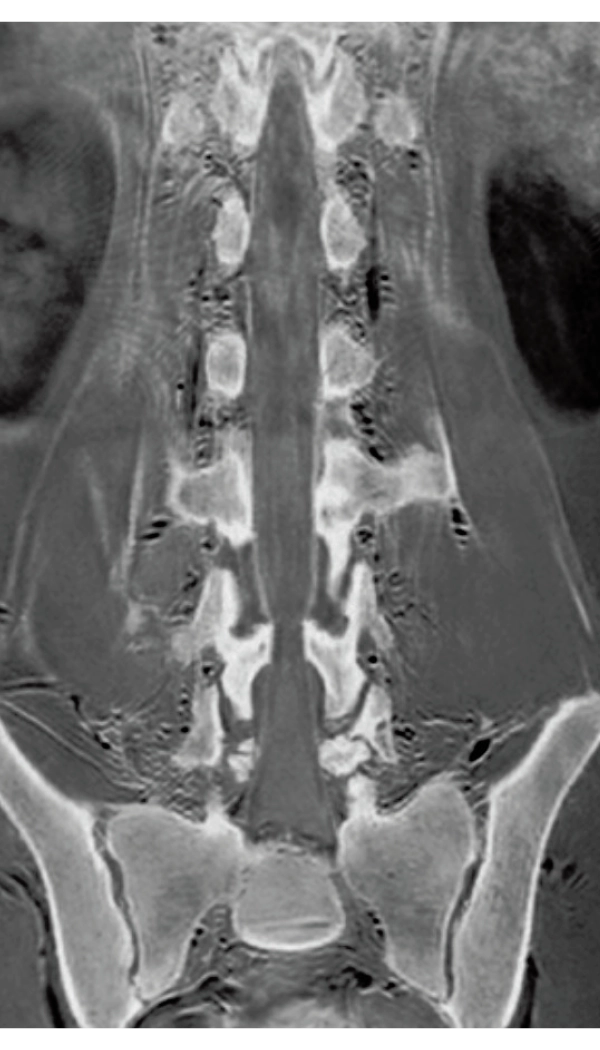

3DisoFSE T2WI

0.75×0.75×1.1(0.55)mm

MPR COR